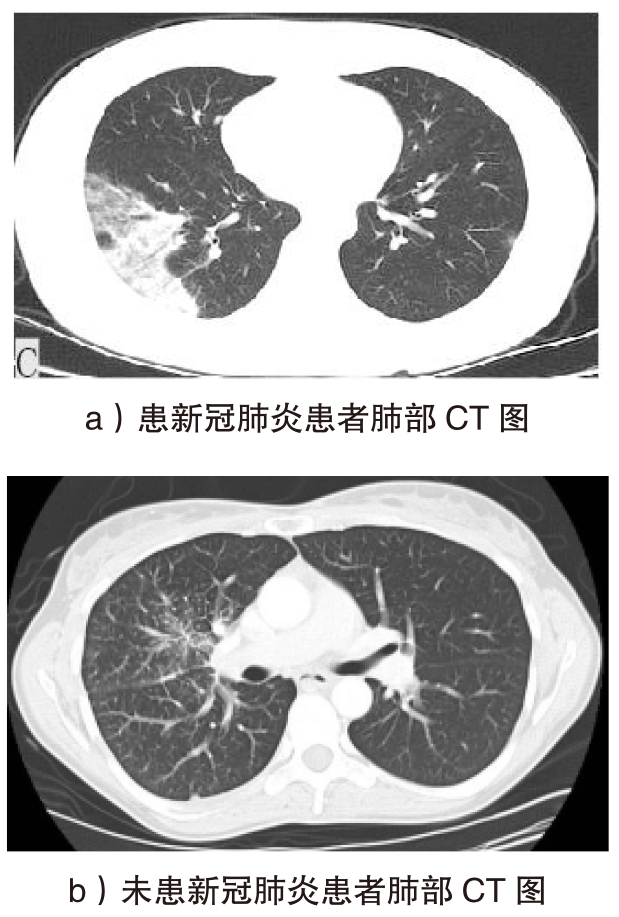

随着智能医疗系统的快速发展,标注数据的匮乏已成为制约研究进展的关键因素之一,知识蒸馏作为一种有效的数据利用策略能够缓解这一问题。然而,在智能医疗领域,模型通常用于替代人工进行影像、数据的诊断,这不仅对医疗信息隐私保护提出了更高要求,还强调了模型精度对诊断结果准确性的决定性影响。因此,文章提出一种结合差分隐私的知识蒸馏方案,并将其应用于图神经网络模型,在知识蒸馏过程中保护用户敏感信息的同时,确保较高的医疗诊断准确率。为验证所提方法的有效性,文章构建了图注意力网络(GAT)模型和卷积神经网络(CNN)模型作为对照组,并采用3种实际医疗图像数据集进行实验。结果表明,文章所提方法在GAT模型的准确率较在CNN模型的准确率有所提升,对应在3个数据集上分别由61%提升至68%、83%提升至93%、67%提升至80%。鉴于GAT模型的高资源开销,文章进一步设计了一种轻量化GAT模型架构。该轻量化模型在显著降低资源消耗的同时,仍保持优于CNN模型的分类性能,从而在差分隐私保护的前提下,有效提升医疗诊断效果。